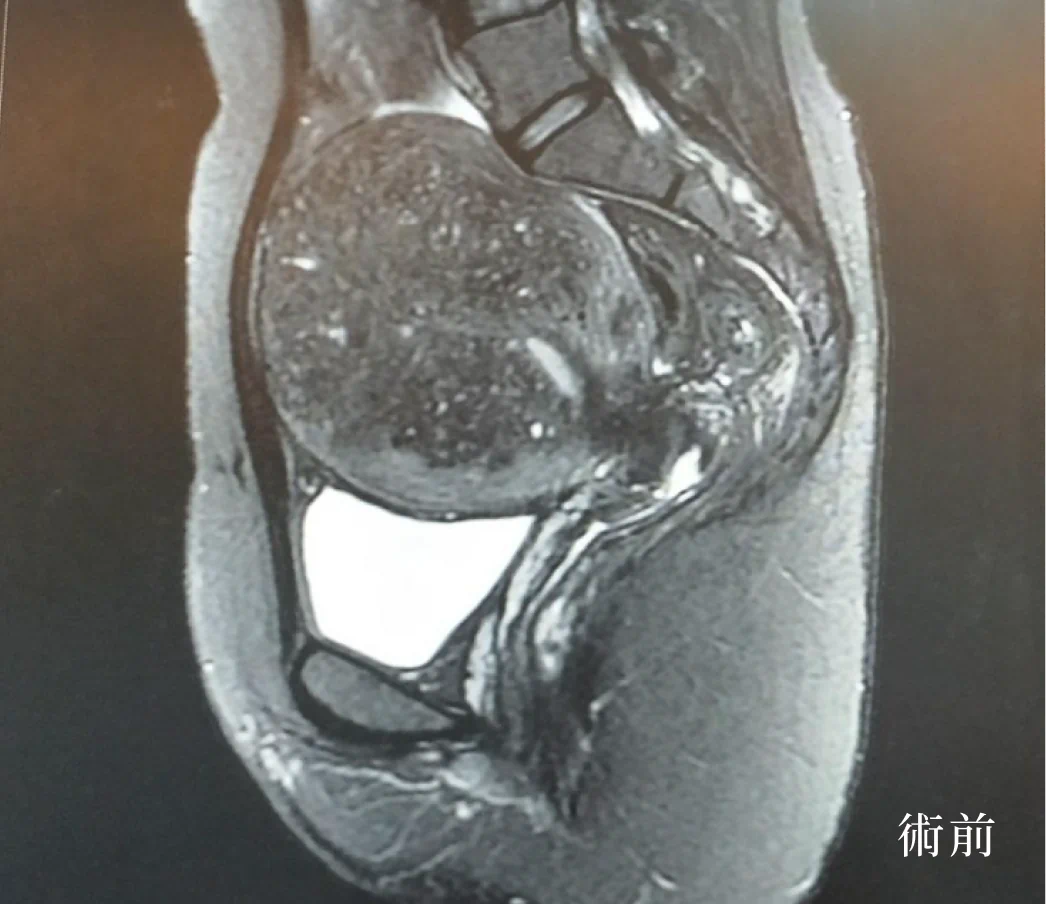

個案在海扶刀治療前,子宮肌瘤最大的約9*8 cm,經由吳昆哲醫師用海扶超音波聚焦消融術後,不僅表皮無傷口,做完手術的隔天即可出院,恢復正常的日常生活及輕鬆的返回職場工作。

生安海扶中心也有專人安排做術後的MRI追蹤,輔導健康生活模式及專線諮詢和子宮保健操,以及持續關心個案在術後身心的狀況,讓個案在術後得到安心又完整的照顧。